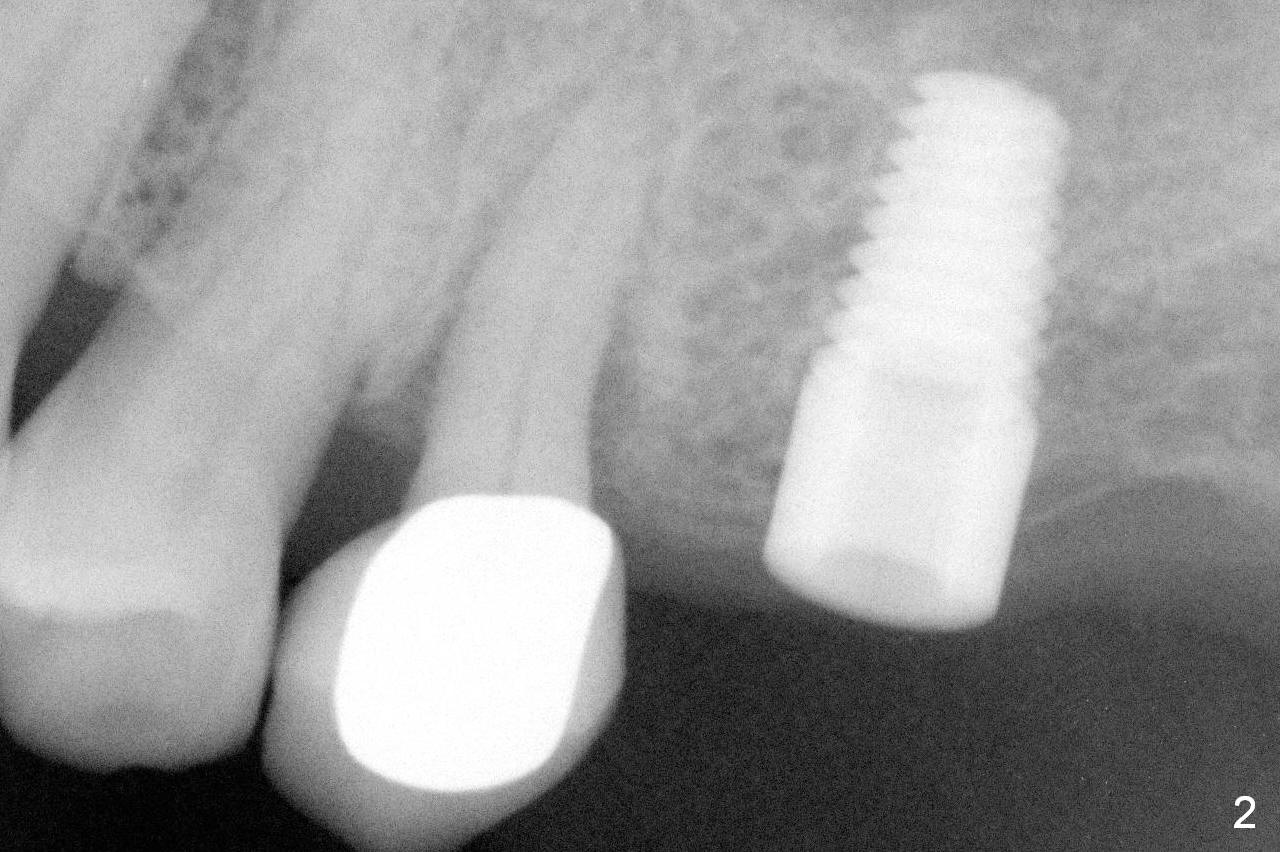

A 73-year-old woman is a possible bruxer with partial edentulism; the tooth #13 had increased periodontal ligament (pdl) space 4 years ago (Fig.1 *).  A 5x14 mm tissue-level implant is placed at the site of #14 (Fig.2).  The implant appears to be osteointegrated in 6 months (Fig.3).  There is crestal bone loss 8 months post cementation (Fig.4 *).  The persistent increased pdl at #13 is most likely associated with occlusal tramua from the tooth #19 (Fig.5 (13 months post cementation of #14)).  Three years post #14 cementation, the tooth #13 has mobililty II (Fig.6); bone density increases around the apical half of the implant (arrowheads).  Normally bone density is the highest coronally where functionality dictates.  This indicates the bone loss is getting worse at #14 as well.